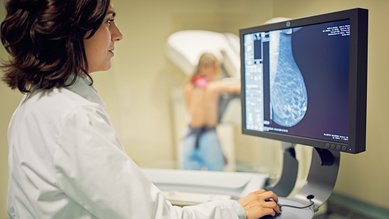

سرطان الثدي

سرطان الثدي هو أكثر أنواع أمراض السرطان شيوعًا بين السيدات في ألمانيا. حيث تُصاب به حوالي 70,000 سيدة في ألمانيا كل عام. ويمكن علاج سرطان الثدي في الكثير من الحالات.